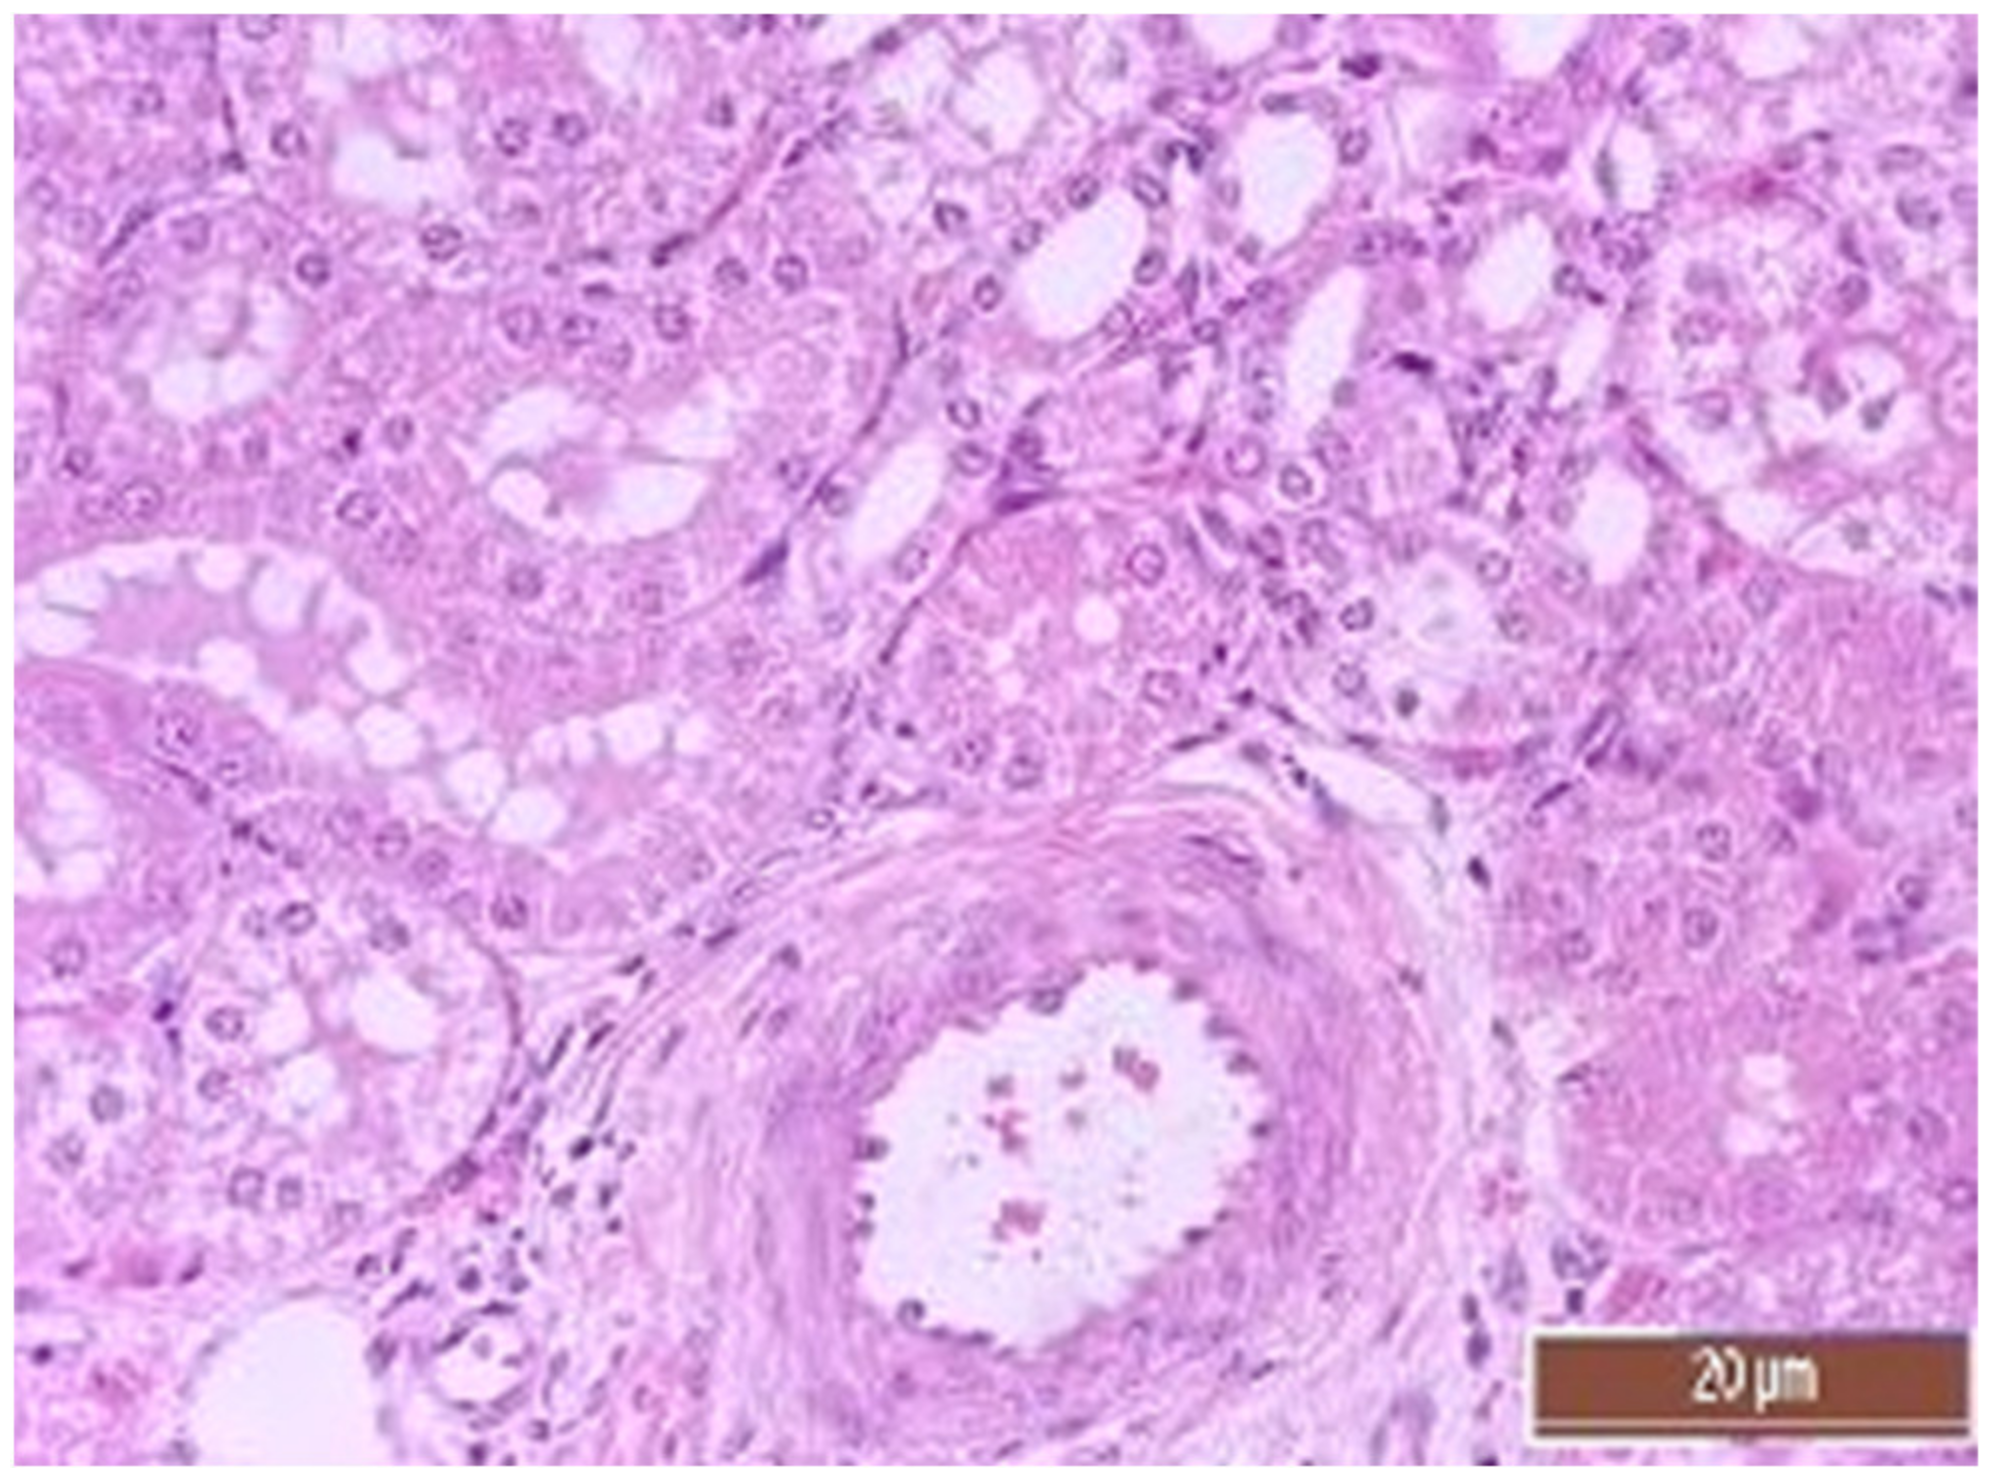

3.2. Pathology of the Liver

3.4. Pathology of Kidneys